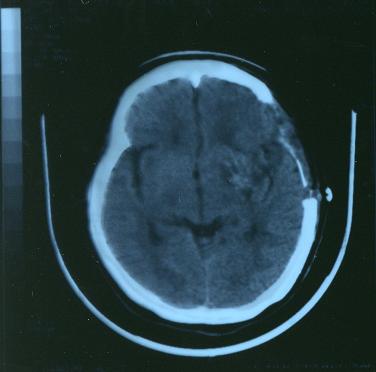

平成15年2

月

18

日の写真

腫れも大分引いて来ました。

損傷している部分が大きいことが良く判ります。

この頃は未だ痛みも分からず意識は全く有りませんでした。